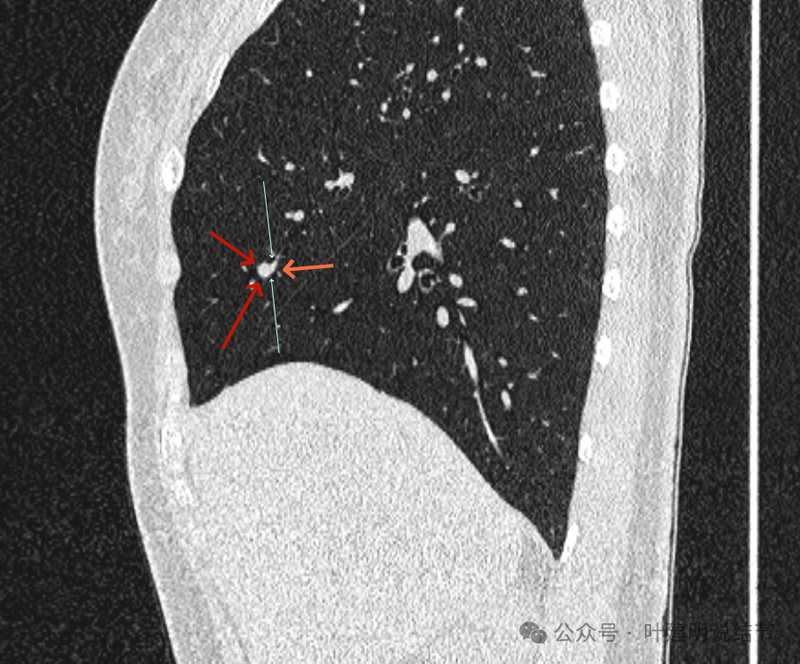

再看冠状位影像:

血管与病灶的关系,两者密度稍不同,天蓝色细箭头所指是分界线。

血管征明显。

血管围着病灶,病灶有膨胀性,表面欠平滑。

不而有膨胀性,血管贴着并被压迫。

边缘欠平滑,邻近血管间隙欠清晰。